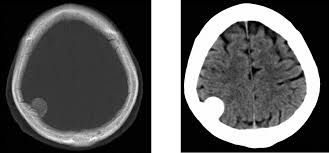

Accidente cerebrovascular e infarto de miocardio con la anticoncepción hormonal contemporánea

El uso de anticonceptivos contemporáneos con estrógeno-progestina y con progestina sola se asoció con un mayor riesgo de accidente cerebrovascular isquémico y, en algunos casos, infarto de miocardio, excepto en el caso del dispositivo intrauterino liberador de levonorgestrel, que no se asoció con ninguno de estos factores. Aunque los riesgos absolutos fueron bajos, los médicos deben incluir esta información en su evaluación de los beneficios y riesgos de prescribir un método anticonceptivo hormonal. BMJ, 12 de febrero de 2025.